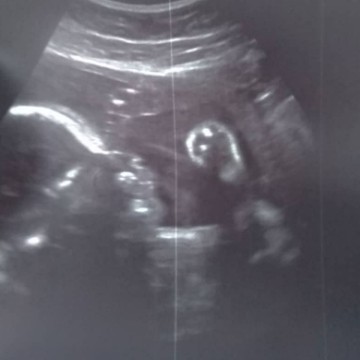

ครบ7เดือนวันนี้แล้ว 21/04/62

แม่ทนคันทนร้อน รวมๆไม่แพ้ท้องเลย แต่ติดที่คันทั้งตัวตอนนี้ ก็ต้องทนเพื่อลูกชายของแม่ แม่รอลูกอยู่นะ ลมหายใจของแม่คือลูก อากาศร้อนๆแบบนี้ แม่คันจนอยากจะร้องไห้ อยู่แอร์ยังคันเลย ป๊าต้องคอยทายาให้ และตี3-4แม่นอนไม่ได้ อีกไม่กี่วันเราก็จะเจอกันแล้วลูกจ๋า แม่กะป๊ารอหนูมาเติมเต็มนะ?